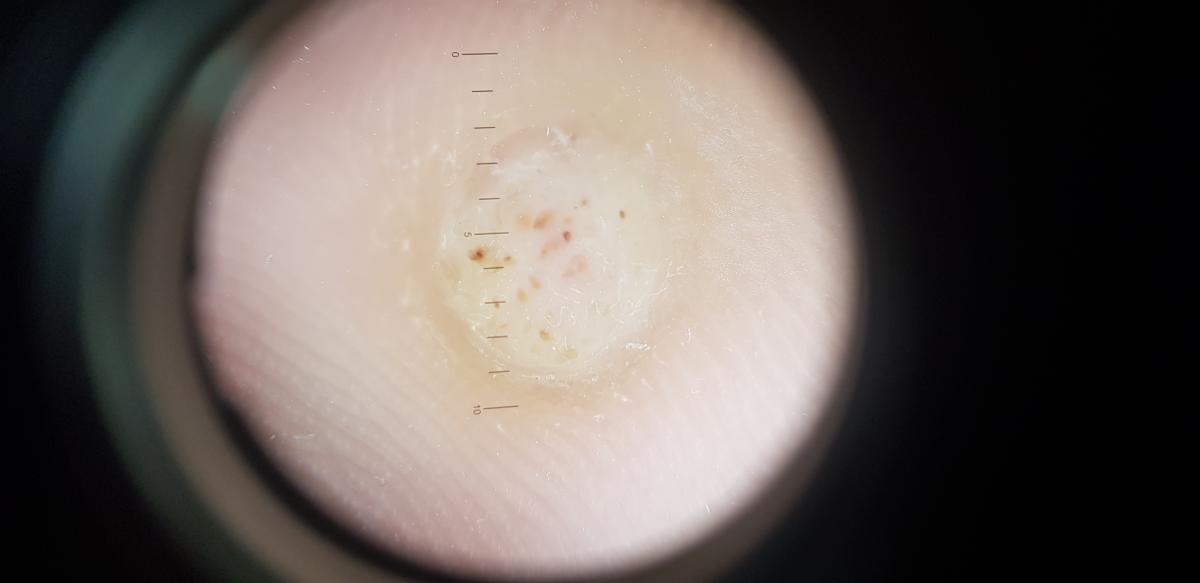

Они характеризуются гиперкератозом, наличием точечных кровоизлияний (тромбированных капилляров, известных как “черные точки”) и часто имитируют мозоли, что затрудняет своевременную диагностику.

При дерматоскопии и внешнем осмотре такой признак, как тромбированные капилляры или черные точки на поверхности нароста, говорят о том, что это бородавка.

Это основной отличительный признак от мозоли. Заражение происходит именно на стопе, потому что она контактирует с внешней средой. Через микротравмы вирусы проникают непосредственно в кожу.